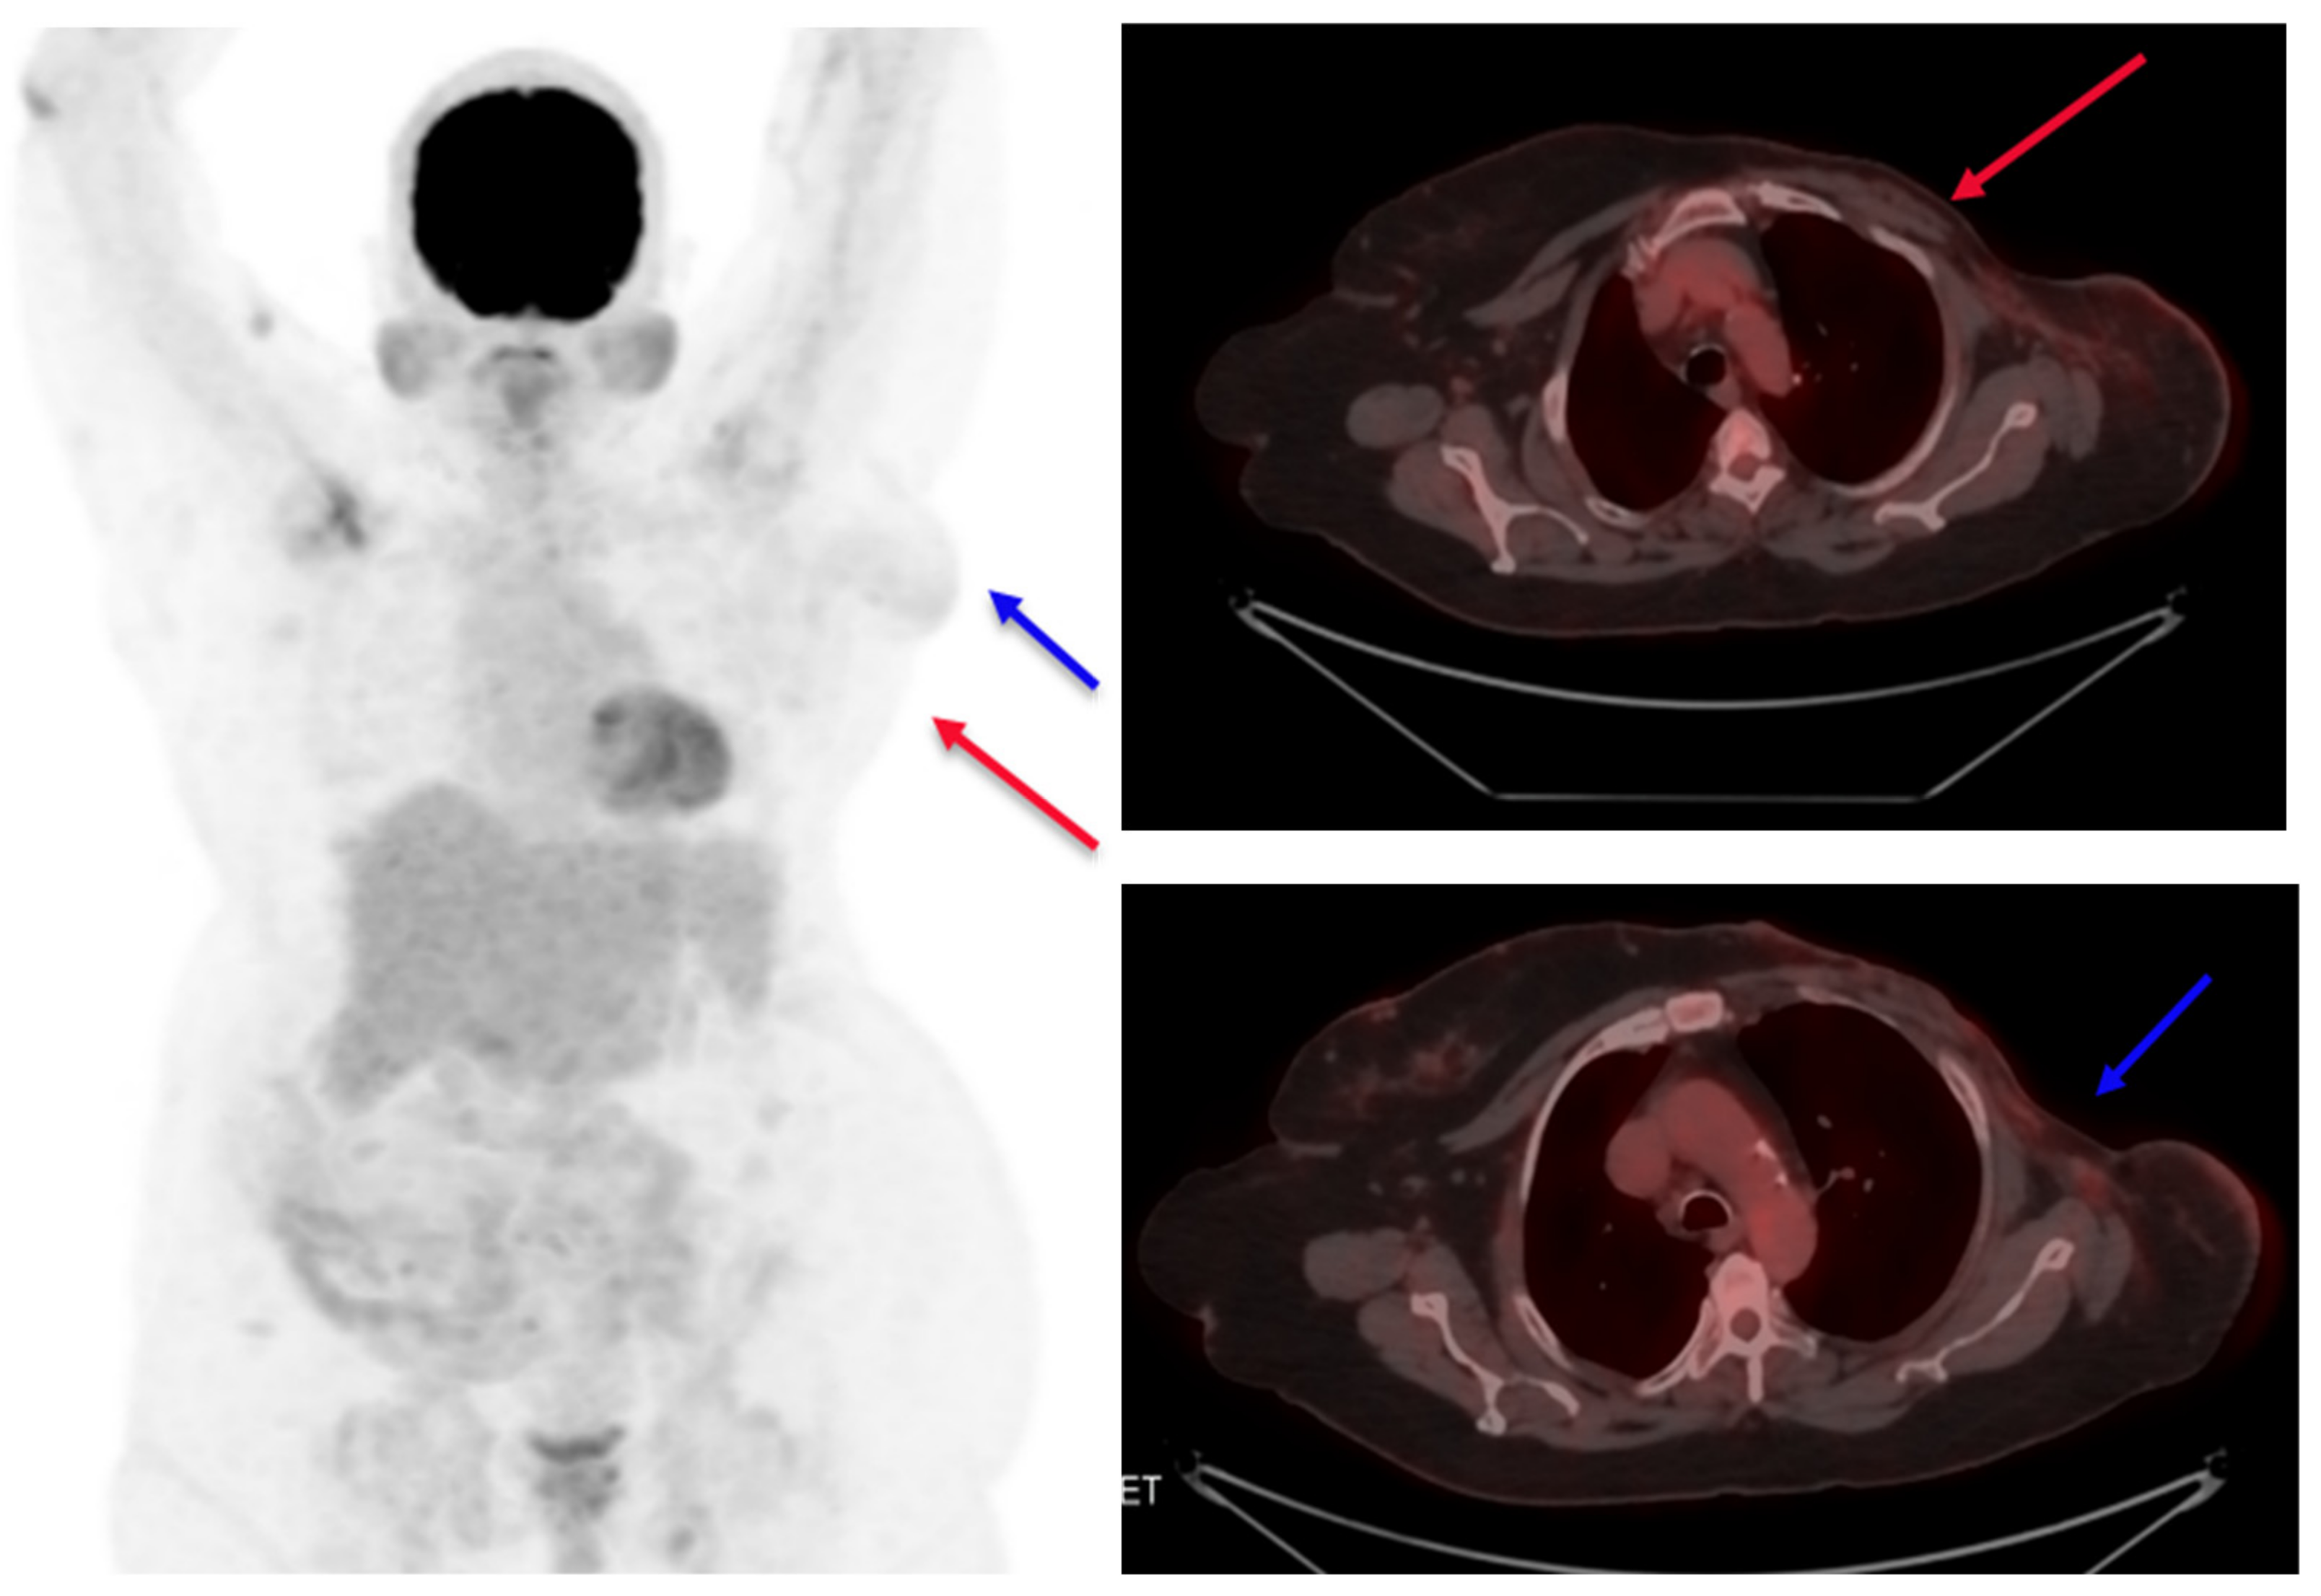

On an initial mammography diagnostic evaluation, a 3 × 2 cm lump was noted in the central and lower outer quadrants of the left breast, which, on further evaluation through ultrasound-guided core needle biopsy, was confirmed as an invasive ductal carcinoma. A pathological examination showed grade II invasive ductal carcinoma of the left breast with axillary lymph nodes with hormone-positive, Her2neu-positive, E-cadherin-positive, and Ki-67 expression of 55 to 60% and of a luminal B type (Figure 1). A whole-body PET CT scan was suggestive of a mass in the lower aspect of the left breast with a few specks of calcifications and left axillary lymphadenopathy (Figure 2). The patient had a previous history of mild anginal symptoms, starting in June 2021, and was evaluated for NSTEMI. The final clinical diagnosis was cT2N1M0-Her2-positive EBC. It was better to proceed with neoadjuvant therapy for three to six cycles and then reassess for surgery.

Figure 2.

Pretreatment PET scan images (A). Primary tumor (Target 1) shown as a red arrow and (B) axillary lymph node (Target 2) shown as a blue arrow.